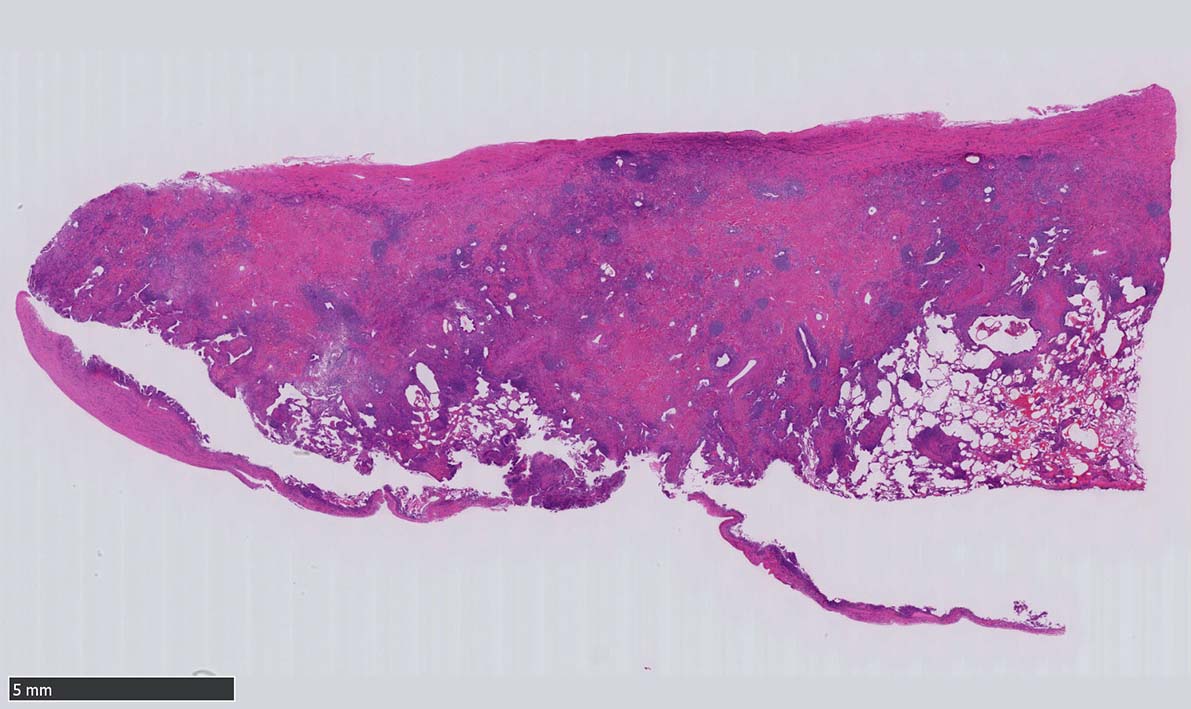

12 x 3.8mm, 腫大した鼠径リンパ節が生検された.--クリックで大きな画像がみられます.|

萎縮した胚中心をマントル細胞が取り囲む濾胞構造がびまん性に認められる. 濾胞間には,形質細胞が密に認められる.

萎縮した胚中心には細血管が侵入する特徴的な所見がある. (Lolli-pop germinal center)